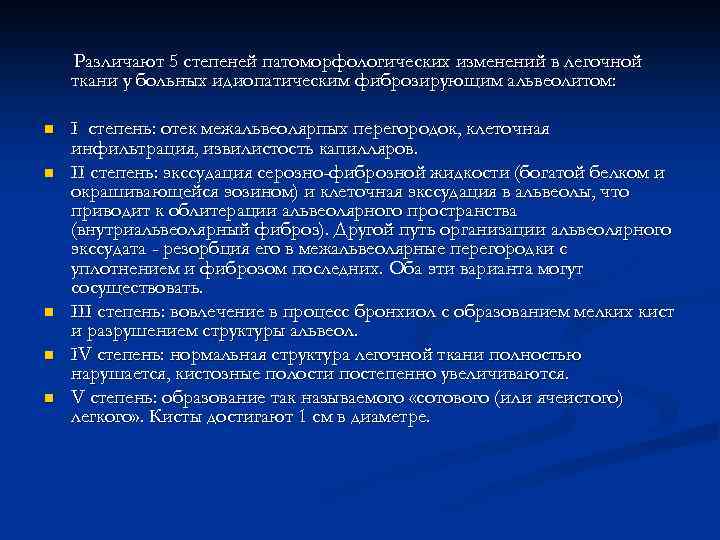

Различают 5 степеней патоморфологических изменений в легочной ткани у больных идиопатическим фиброзирующим альвеолитом: n n n I степень: отек межальвеолярпых перегородок, клеточная инфильтрация, извилистость капилляров. II степень: экссудация серозно-фиброзной жидкости (богатой белком и окрашивающейся эозином) и клеточная экссудация в альвеолы, что приводит к облитерации альвеолярного пространства (внутриальвеолярный фиброз). Другой путь организации альвеолярного экссудата - резорбция его в межальвеолярные перегородки с уплотнением и фиброзом последних. Оба эти варианта могут сосуществовать. III степень: вовлечение в процесс бронхиол с образованием мелких кист и разрушением структуры альвеол. IV степень: нормальная структура легочной ткани полностью нарушается, кистозные полости постепенно увеличиваются. V степень: образование так называемого «сотового (или ячеистого) легкого» . Кисты достигают 1 см в диаметре.